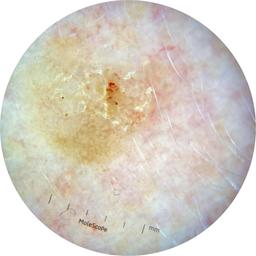

ISIC_3176953

Information

2135 x 2135

Clinical

Field Value

acquisition_day 410

age_approx 40

anatom_site_1 Head and neck

anatom_site_general head/neck

concomitant_biopsy False

diagnosis_1 Malignant

diagnosis_2 Malignant adnexal epithelial proliferations - Follicular

diagnosis_3 Basal cell carcinoma

diagnosis_confirm_type single image expert consensus

family_hx_mm False

fitzpatrick_skin_type I

image_manipulation instrument only

image_type dermoscopic

lesion_id IL_4059380

patient_id IP_8700330

personal_hx_mm True

sex female